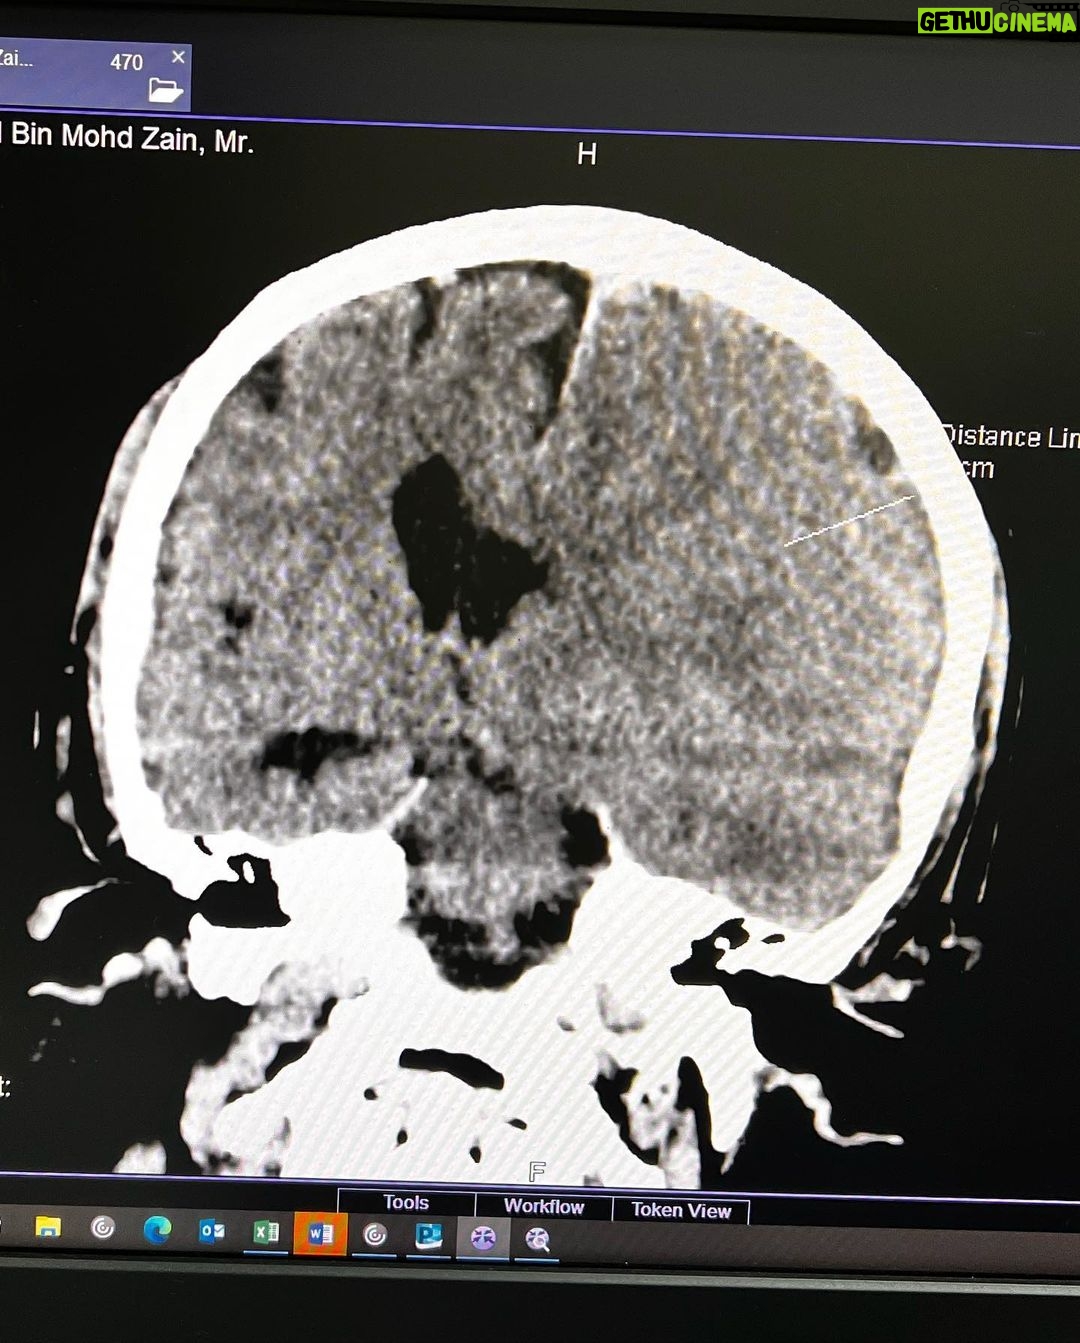

Caption : Kalau anyone you know jatuh kepala terhentak, luaran memang takde apa tapi dalaman maybe boleh jadi pendarahan perlahan. Sejurus dari terjatuh, bila check X-Ray dan CT scan it will tell you nothing, semua clear saja, but 2-3weeks later could turn into your biggest nightmare when the blood has flooded a big part of your brain. My dad realised something was wrong hampir sebulan lepas jatuh, when suddenly he couldn’t really move his right leg. Macam lagging. Sebab dia jatuh terhentak dahi kiri, bila anggota belah kanan yang terjejas, we knew it must be the brain. I picked him up and asked about his very very recent trip to Acheh, he said “Bila Daddy pergi Acheh?”. Ya Allah this very man, is my dad, someone who was very sharp and opinionated, tiba-tiba sangat blur dan slow, jawab sepatah-sepatah. So I spent the whole day uruskan dia, consulted two specialists and one neurosurgeon and when he is finally admitted that night to prepare him for his surgery the following day, he told the family “Daddy tadi drive sendiri datang sini”. My heart sank, I was frantic with worry — takutnya lagi lambat ni lagi banyak memori dia hilang. The brain surgery went well atas izin Allah, thank you to everyone involved. Doktor kata kalau lewat sikit je lagi memang boleh hilang keupayaan bercakap, keupayaan bernafas dan seterusnya koma, sebab otak dah compressed terlalu banyak darah. I jot this here as a reminder for all of us to always jangan tangguh-tangguh kalau hati dah tergerak. Daddy masih tak ingat I bawak dia pi hospital hari tu. Nasib baik kita selfie.Likes : 168141

Caption : Kalau anyone you know jatuh kepala terhentak, luaran memang takde apa tapi dalaman maybe boleh jadi pendarahan perlahan. Sejurus dari terjatuh, bila check X-Ray dan CT scan it will tell you nothing, semua clear saja, but 2-3weeks later could turn into your biggest nightmare when the blood has flooded a big part of your brain. My dad realised something was wrong hampir sebulan lepas jatuh, when suddenly he couldn’t really move his right leg. Macam lagging. Sebab dia jatuh terhentak dahi kiri, bila anggota belah kanan yang terjejas, we knew it must be the brain. I picked him up and asked about his very very recent trip to Acheh, he said “Bila Daddy pergi Acheh?”. Ya Allah this very man, is my dad, someone who was very sharp and opinionated, tiba-tiba sangat blur dan slow, jawab sepatah-sepatah. So I spent the whole day uruskan dia, consulted two specialists and one neurosurgeon and when he is finally admitted that night to prepare him for his surgery the following day, he told the family “Daddy tadi drive sendiri datang sini”. My heart sank, I was frantic with worry — takutnya lagi lambat ni lagi banyak memori dia hilang. The brain surgery went well atas izin Allah, thank you to everyone involved. Doktor kata kalau lewat sikit je lagi memang boleh hilang keupayaan bercakap, keupayaan bernafas dan seterusnya koma, sebab otak dah compressed terlalu banyak darah. I jot this here as a reminder for all of us to always jangan tangguh-tangguh kalau hati dah tergerak. Daddy masih tak ingat I bawak dia pi hospital hari tu. Nasib baik kita selfie.Likes : 168141

Caption : Kalau anyone you know jatuh kepala terhentak, luaran memang takde apa tapi dalaman maybe boleh jadi pendarahan perlahan. Sejurus dari terjatuh, bila check X-Ray dan CT scan it will tell you nothing, semua clear saja, but 2-3weeks later could turn into your biggest nightmare when the blood has flooded a big part of your brain. My dad realised something was wrong hampir sebulan lepas jatuh, when suddenly he couldn’t really move his right leg. Macam lagging. Sebab dia jatuh terhentak dahi kiri, bila anggota belah kanan yang terjejas, we knew it must be the brain. I picked him up and asked about his very very recent trip to Acheh, he said “Bila Daddy pergi Acheh?”. Ya Allah this very man, is my dad, someone who was very sharp and opinionated, tiba-tiba sangat blur dan slow, jawab sepatah-sepatah. So I spent the whole day uruskan dia, consulted two specialists and one neurosurgeon and when he is finally admitted that night to prepare him for his surgery the following day, he told the family “Daddy tadi drive sendiri datang sini”. My heart sank, I was frantic with worry — takutnya lagi lambat ni lagi banyak memori dia hilang. The brain surgery went well atas izin Allah, thank you to everyone involved. Doktor kata kalau lewat sikit je lagi memang boleh hilang keupayaan bercakap, keupayaan bernafas dan seterusnya koma, sebab otak dah compressed terlalu banyak darah. I jot this here as a reminder for all of us to always jangan tangguh-tangguh kalau hati dah tergerak. Daddy masih tak ingat I bawak dia pi hospital hari tu. Nasib baik kita selfie.Likes : 168141

Caption : Kalau anyone you know jatuh kepala terhentak, luaran memang takde apa tapi dalaman maybe boleh jadi pendarahan perlahan. Sejurus dari terjatuh, bila check X-Ray dan CT scan it will tell you nothing, semua clear saja, but 2-3weeks later could turn into your biggest nightmare when the blood has flooded a big part of your brain. My dad realised something was wrong hampir sebulan lepas jatuh, when suddenly he couldn’t really move his right leg. Macam lagging. Sebab dia jatuh terhentak dahi kiri, bila anggota belah kanan yang terjejas, we knew it must be the brain. I picked him up and asked about his very very recent trip to Acheh, he said “Bila Daddy pergi Acheh?”. Ya Allah this very man, is my dad, someone who was very sharp and opinionated, tiba-tiba sangat blur dan slow, jawab sepatah-sepatah. So I spent the whole day uruskan dia, consulted two specialists and one neurosurgeon and when he is finally admitted that night to prepare him for his surgery the following day, he told the family “Daddy tadi drive sendiri datang sini”. My heart sank, I was frantic with worry — takutnya lagi lambat ni lagi banyak memori dia hilang. The brain surgery went well atas izin Allah, thank you to everyone involved. Doktor kata kalau lewat sikit je lagi memang boleh hilang keupayaan bercakap, keupayaan bernafas dan seterusnya koma, sebab otak dah compressed terlalu banyak darah. I jot this here as a reminder for all of us to always jangan tangguh-tangguh kalau hati dah tergerak. Daddy masih tak ingat I bawak dia pi hospital hari tu. Nasib baik kita selfie.Likes : 168141

Caption : Kalau anyone you know jatuh kepala terhentak, luaran memang takde apa tapi dalaman maybe boleh jadi pendarahan perlahan. Sejurus dari terjatuh, bila check X-Ray dan CT scan it will tell you nothing, semua clear saja, but 2-3weeks later could turn into your biggest nightmare when the blood has flooded a big part of your brain. My dad realised something was wrong hampir sebulan lepas jatuh, when suddenly he couldn’t really move his right leg. Macam lagging. Sebab dia jatuh terhentak dahi kiri, bila anggota belah kanan yang terjejas, we knew it must be the brain. I picked him up and asked about his very very recent trip to Acheh, he said “Bila Daddy pergi Acheh?”. Ya Allah this very man, is my dad, someone who was very sharp and opinionated, tiba-tiba sangat blur dan slow, jawab sepatah-sepatah. So I spent the whole day uruskan dia, consulted two specialists and one neurosurgeon and when he is finally admitted that night to prepare him for his surgery the following day, he told the family “Daddy tadi drive sendiri datang sini”. My heart sank, I was frantic with worry — takutnya lagi lambat ni lagi banyak memori dia hilang. The brain surgery went well atas izin Allah, thank you to everyone involved. Doktor kata kalau lewat sikit je lagi memang boleh hilang keupayaan bercakap, keupayaan bernafas dan seterusnya koma, sebab otak dah compressed terlalu banyak darah. I jot this here as a reminder for all of us to always jangan tangguh-tangguh kalau hati dah tergerak. Daddy masih tak ingat I bawak dia pi hospital hari tu. Nasib baik kita selfie.Likes : 168141

Caption : Kalau anyone you know jatuh kepala terhentak, luaran memang takde apa tapi dalaman maybe boleh jadi pendarahan perlahan. Sejurus dari terjatuh, bila check X-Ray dan CT scan it will tell you nothing, semua clear saja, but 2-3weeks later could turn into your biggest nightmare when the blood has flooded a big part of your brain. My dad realised something was wrong hampir sebulan lepas jatuh, when suddenly he couldn’t really move his right leg. Macam lagging. Sebab dia jatuh terhentak dahi kiri, bila anggota belah kanan yang terjejas, we knew it must be the brain. I picked him up and asked about his very very recent trip to Acheh, he said “Bila Daddy pergi Acheh?”. Ya Allah this very man, is my dad, someone who was very sharp and opinionated, tiba-tiba sangat blur dan slow, jawab sepatah-sepatah. So I spent the whole day uruskan dia, consulted two specialists and one neurosurgeon and when he is finally admitted that night to prepare him for his surgery the following day, he told the family “Daddy tadi drive sendiri datang sini”. My heart sank, I was frantic with worry — takutnya lagi lambat ni lagi banyak memori dia hilang. The brain surgery went well atas izin Allah, thank you to everyone involved. Doktor kata kalau lewat sikit je lagi memang boleh hilang keupayaan bercakap, keupayaan bernafas dan seterusnya koma, sebab otak dah compressed terlalu banyak darah. I jot this here as a reminder for all of us to always jangan tangguh-tangguh kalau hati dah tergerak. Daddy masih tak ingat I bawak dia pi hospital hari tu. Nasib baik kita selfie.Likes : 168141

Caption : Kalau anyone you know jatuh kepala terhentak, luaran memang takde apa tapi dalaman maybe boleh jadi pendarahan perlahan. Sejurus dari terjatuh, bila check X-Ray dan CT scan it will tell you nothing, semua clear saja, but 2-3weeks later could turn into your biggest nightmare when the blood has flooded a big part of your brain. My dad realised something was wrong hampir sebulan lepas jatuh, when suddenly he couldn’t really move his right leg. Macam lagging. Sebab dia jatuh terhentak dahi kiri, bila anggota belah kanan yang terjejas, we knew it must be the brain. I picked him up and asked about his very very recent trip to Acheh, he said “Bila Daddy pergi Acheh?”. Ya Allah this very man, is my dad, someone who was very sharp and opinionated, tiba-tiba sangat blur dan slow, jawab sepatah-sepatah. So I spent the whole day uruskan dia, consulted two specialists and one neurosurgeon and when he is finally admitted that night to prepare him for his surgery the following day, he told the family “Daddy tadi drive sendiri datang sini”. My heart sank, I was frantic with worry — takutnya lagi lambat ni lagi banyak memori dia hilang. The brain surgery went well atas izin Allah, thank you to everyone involved. Doktor kata kalau lewat sikit je lagi memang boleh hilang keupayaan bercakap, keupayaan bernafas dan seterusnya koma, sebab otak dah compressed terlalu banyak darah. I jot this here as a reminder for all of us to always jangan tangguh-tangguh kalau hati dah tergerak. Daddy masih tak ingat I bawak dia pi hospital hari tu. Nasib baik kita selfie.Likes : 168141

Caption : Kalau anyone you know jatuh kepala terhentak, luaran memang takde apa tapi dalaman maybe boleh jadi pendarahan perlahan. Sejurus dari terjatuh, bila check X-Ray dan CT scan it will tell you nothing, semua clear saja, but 2-3weeks later could turn into your biggest nightmare when the blood has flooded a big part of your brain. My dad realised something was wrong hampir sebulan lepas jatuh, when suddenly he couldn’t really move his right leg. Macam lagging. Sebab dia jatuh terhentak dahi kiri, bila anggota belah kanan yang terjejas, we knew it must be the brain. I picked him up and asked about his very very recent trip to Acheh, he said “Bila Daddy pergi Acheh?”. Ya Allah this very man, is my dad, someone who was very sharp and opinionated, tiba-tiba sangat blur dan slow, jawab sepatah-sepatah. So I spent the whole day uruskan dia, consulted two specialists and one neurosurgeon and when he is finally admitted that night to prepare him for his surgery the following day, he told the family “Daddy tadi drive sendiri datang sini”. My heart sank, I was frantic with worry — takutnya lagi lambat ni lagi banyak memori dia hilang. The brain surgery went well atas izin Allah, thank you to everyone involved. Doktor kata kalau lewat sikit je lagi memang boleh hilang keupayaan bercakap, keupayaan bernafas dan seterusnya koma, sebab otak dah compressed terlalu banyak darah. I jot this here as a reminder for all of us to always jangan tangguh-tangguh kalau hati dah tergerak. Daddy masih tak ingat I bawak dia pi hospital hari tu. Nasib baik kita selfie.Likes : 168141

Caption : Kalau anyone you know jatuh kepala terhentak, luaran memang takde apa tapi dalaman maybe boleh jadi pendarahan perlahan. Sejurus dari terjatuh, bila check X-Ray dan CT scan it will tell you nothing, semua clear saja, but 2-3weeks later could turn into your biggest nightmare when the blood has flooded a big part of your brain. My dad realised something was wrong hampir sebulan lepas jatuh, when suddenly he couldn’t really move his right leg. Macam lagging. Sebab dia jatuh terhentak dahi kiri, bila anggota belah kanan yang terjejas, we knew it must be the brain. I picked him up and asked about his very very recent trip to Acheh, he said “Bila Daddy pergi Acheh?”. Ya Allah this very man, is my dad, someone who was very sharp and opinionated, tiba-tiba sangat blur dan slow, jawab sepatah-sepatah. So I spent the whole day uruskan dia, consulted two specialists and one neurosurgeon and when he is finally admitted that night to prepare him for his surgery the following day, he told the family “Daddy tadi drive sendiri datang sini”. My heart sank, I was frantic with worry — takutnya lagi lambat ni lagi banyak memori dia hilang. The brain surgery went well atas izin Allah, thank you to everyone involved. Doktor kata kalau lewat sikit je lagi memang boleh hilang keupayaan bercakap, keupayaan bernafas dan seterusnya koma, sebab otak dah compressed terlalu banyak darah. I jot this here as a reminder for all of us to always jangan tangguh-tangguh kalau hati dah tergerak. Daddy masih tak ingat I bawak dia pi hospital hari tu. Nasib baik kita selfie.Likes : 168141

Caption : Kalau anyone you know jatuh kepala terhentak, luaran memang takde apa tapi dalaman maybe boleh jadi pendarahan perlahan. Sejurus dari terjatuh, bila check X-Ray dan CT scan it will tell you nothing, semua clear saja, but 2-3weeks later could turn into your biggest nightmare when the blood has flooded a big part of your brain. My dad realised something was wrong hampir sebulan lepas jatuh, when suddenly he couldn’t really move his right leg. Macam lagging. Sebab dia jatuh terhentak dahi kiri, bila anggota belah kanan yang terjejas, we knew it must be the brain. I picked him up and asked about his very very recent trip to Acheh, he said “Bila Daddy pergi Acheh?”. Ya Allah this very man, is my dad, someone who was very sharp and opinionated, tiba-tiba sangat blur dan slow, jawab sepatah-sepatah. So I spent the whole day uruskan dia, consulted two specialists and one neurosurgeon and when he is finally admitted that night to prepare him for his surgery the following day, he told the family “Daddy tadi drive sendiri datang sini”. My heart sank, I was frantic with worry — takutnya lagi lambat ni lagi banyak memori dia hilang. The brain surgery went well atas izin Allah, thank you to everyone involved. Doktor kata kalau lewat sikit je lagi memang boleh hilang keupayaan bercakap, keupayaan bernafas dan seterusnya koma, sebab otak dah compressed terlalu banyak darah. I jot this here as a reminder for all of us to always jangan tangguh-tangguh kalau hati dah tergerak. Daddy masih tak ingat I bawak dia pi hospital hari tu. Nasib baik kita selfie.Likes : 168141